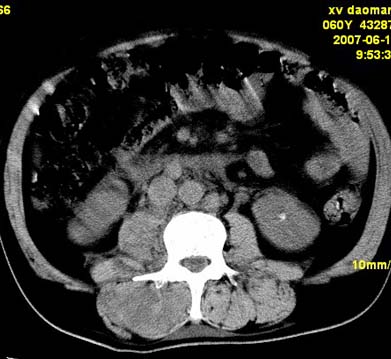

以下是引用刘明在2007-6-26 16:00:00的发言:[br][br]右侧竖直肌及腰大肌肿胀,脂肪间隙难辨,腹膜后血管旁见多个肿大淋巴结影,椎体附件右侧有压迫吸收、未见硬化迹象,考虑椎旁冷脓肿可能[br]左侧肾盂内可见高密度影,周围有毛刺,本图象是平扫,不是增强,应该是结石[br]

以下是引用hhcckk在2007-6-27 9:41:00的发言:[br]肾周筋膜增厚,胰腺影肥大,楼主是考我们了,我考虑是胰腺炎引起的腰部感染,形成的蓝棕色斑,也称gray-turner征,另外腹膜后怎么这么多的淋巴结,转移也要考虑[br]结核三个月没有骨破坏?寒性脓肿累及到竖脊肌的少见,所以我考虑结核的可能性不太大[br]左肾内高密度影,密度不太均匀,左肾有积水的表现,考虑是结石[br]期待楼主老师的结果